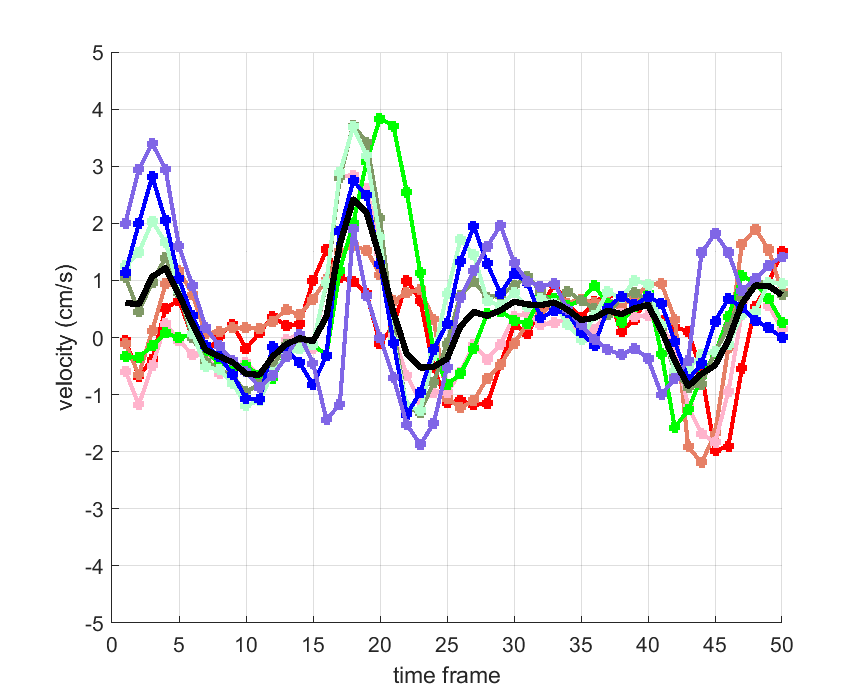

Time courses of the estimated translational component per subject, frame, slice and volume along the 3 velocity directions x, y and z are presented in Fig.6 - Fig.8.